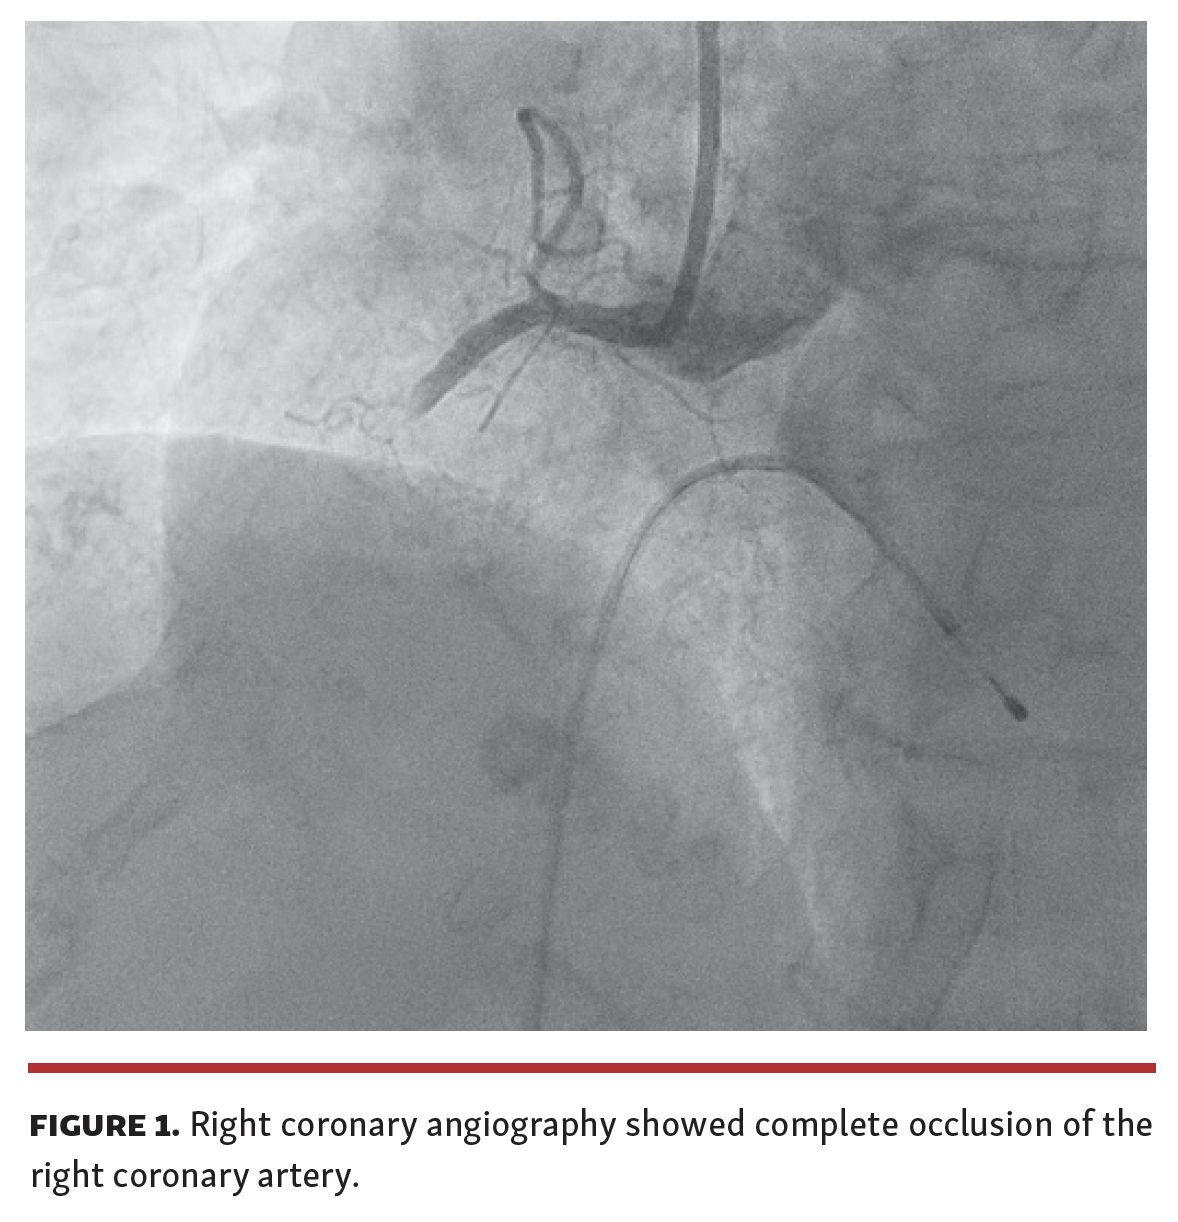

An 89-year-old woman was referred to our cath lab for a primary percutaneous coronary intervention (pPCI) following electrocardiographic evidence of inferior ST-segment elevation myocardial infarction. A coronary angiography revealed single-vessel disease with complete occlusion of the right coronary artery (Figure 1). After crossing the occlusion with a guidewire, we proceeded with manual thrombectomy using the Eliminate Aspiration Catheter (Terumo Europe). We slowly advanced through the occlusion with the thrombus aspirator catheter a few times, until we noticed a sudden interruption of blood flow in the syringe connected to the catheter. We removed the device to check and surprisingly a huge red thrombus remained enveloped between the tip of the suction catheter and the Y-connector of the guiding catheter. We gently disconnected the Y-connector and removed the thrombus en bloc by performing a mild saline wash of the suction catheter. The thrombus, placed lengthwise on sterile gauze, was about 6 cm long (Figure 2). To our knowledge, this is the longest coronary thrombus ever reported to be removed in its entirety. We successfully completed the pPCI with the implantation of a 3 x 26 mm drug-eluting stent (Figure 3).